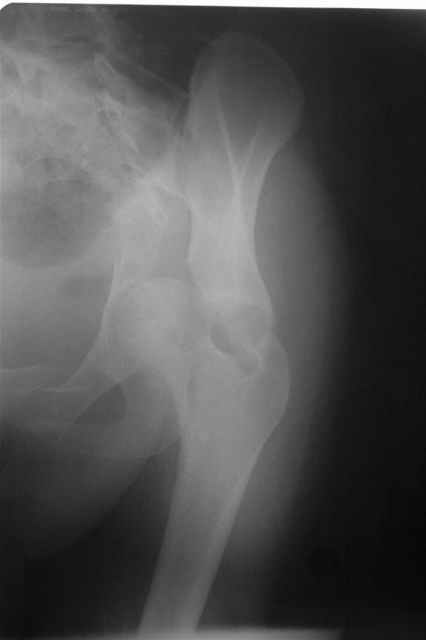

acetabular fracture

Уважаемые коллеги, Поступила 21 года барышня после автоаварии.

Интересно было бы ваше мнение какой доступ оптимален, положение на животе или на боку? Заранее признателен, Евгений И.Чекашкин